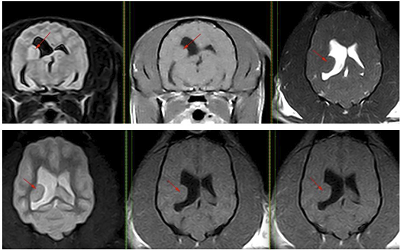

Advanced imaging, such as magnetic resonance imaging (MRI) (left) or computed tomography (CT) scans, is necessary to be able to actually see the structure of the brain. By imaging the brain, veterinarians are able to diagnose diseases such as brain tumors or hydrocephalus (water on the brain) which can cause seizures. Essentially, MRI scans serve to rule out structural abnormalities. Veterinary neurologist Dr. Clare Rusbridge published two YouTube videos on MRI scanning epilepsy patients in May 2024. The first one is titled "Epileptic pet -- should I get a MRI?", and the second one is "MRI Epilepsy Protocol for pets: A Step-by-Step Guide".

In a 2012 report, UK neurology researchers examined the magnetic resonance images (MRIs) of 85 cavaliers, looking for a relationship between Chiari-like malformation (CM), ventriculomegaly, and seizures in the dogs. The 85 CKCSs all had CM; 27 of them also had had seizures. They found no association between CM, ventriculomegaly, and the seizures. The seizures were classified as having partial onset -- meaning that they occur in in one area of the brain, unlike generalized seizures which typically affect nerve cells throughout the brain -- in 61% of the dogs. They also stated that "Another cause of recurrent seizures in CKCS (such as familial epilepsy) is suspected, as previously reported."